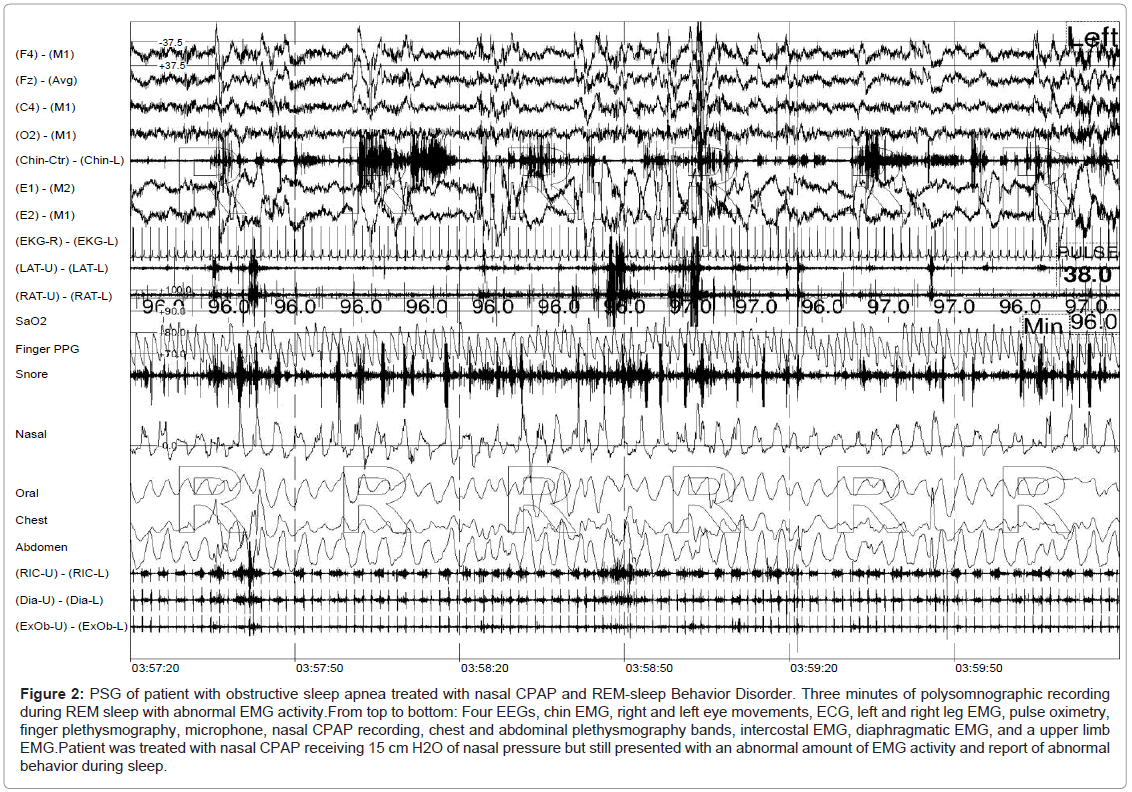

The first PSG at the end of the 4 weeks of sleep logs showed an abnormal presence of chin and limb EMG tone during REM sleep with a variable presence of leg movements, small arm movements, and vocalization (Figures 1 and 2). Using the criteria outlined for the scoring of high EMG during REM sleep, all patients spent more than 20% of the total REM sleep time with elevated EMG, with the inclusion of the EMG bursts tabulated from all recorded muscles. However, only 14 subjects spent 50% or more of the total REM sleep time with elevated EMG. These 14 subjects included all patients with associated neurological disorders.

sleep-disorders-therapy-obstructive-sleep

Figure 2: PSG of patient with obstructive sleep apnea treated with nasal CPAP and REM-sleep Behavior Disorder. Three minutes of polysomnographic recording during REM sleep with abnormal EMG activity.From top to bottom: Four EEGs, chin EMG, right and left eye movements, ECG, left and right leg EMG, pulse oximetry, finger plethysmography, microphone, nasal CPAP recording, chest and abdominal plethysmography bands, intercostal EMG, diaphragmatic EMG, and a upper limb EMG.Patient was treated with nasal CPAP receiving 15 cm H2O of nasal pressure but still presented with an abnormal amount of EMG activity and report of abnormal behavior during sleep.